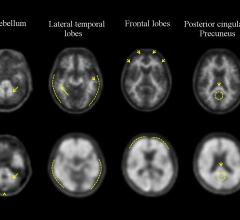

Piramal Imaging announced that WVU Healthcare in West Virginia, is the first center in the United States to perform commercial scans using Neuraceq.